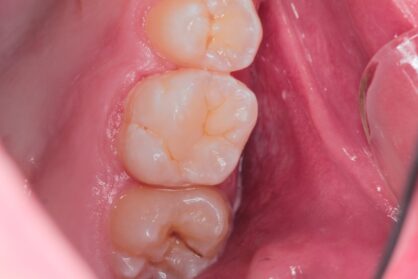

Приклади робіт лікаря-стоматолога

Естетична реставрація. До / після

Сучасні композиційні матеріали для реставрацій ідеально відновлюють естетику зубного ряду. Лікар підбирає прозорість та відтінок матеріалу аби пролікований зуб не відрізнявся від сусідніх здорових.

Вид матеріалів підбирає лікар залежно від конкретного випадку, виду карієсу, локалізації ураження.